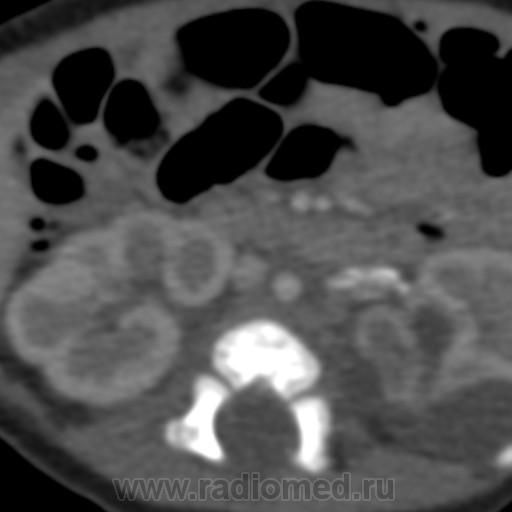

Девочка, 1 месяц, по УЗИ - кисты в области верхнего полюса левой почки. Сделали КТ, кисты оказались уретерогидронефрозом верхней половины удвоенной почки, с отсутствием функции. А вот что за кальцинаты по ходу почечной вены???